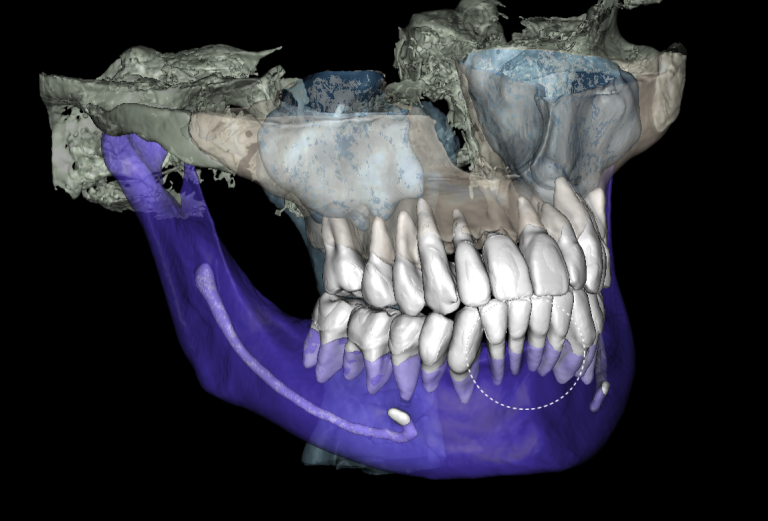

Diagnocat radiological report features an “Conditions with low probability” function. In this mode, teeth marked as “Low probability” are highlighted in yellow. Conditions such as caries and periapical lesions with a probability ranging from 30% to 50%

For example, in the area of tooth 22 (Universal 10), there is a label indicating “signs of caries.” However, they are poorly visualized at the CBCT

Additionally, thanks to the “Conditions with low probability,” signs of caries have been detected on the distal surface of tooth 24 (Universal 12)

If the probability percentage is over 50%, the teeth are highlighted in red, and the report contains information about the localization and depth of the lesions

The presence of caries on the distal and mesial surfaces of tooth 47 (Universal 31) has been clinically confirmed